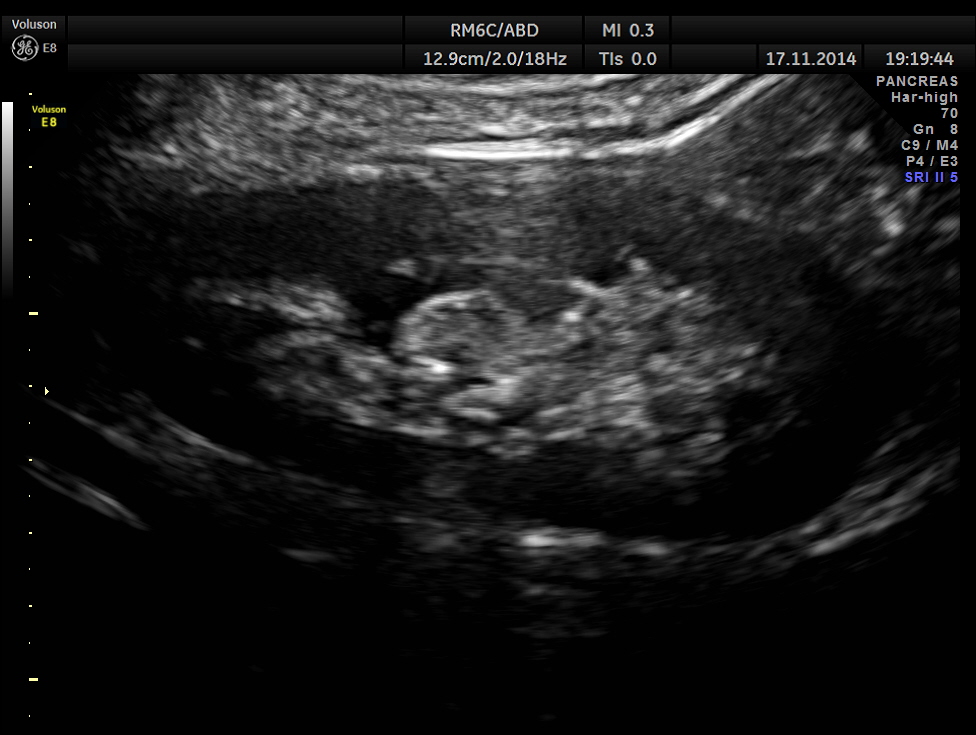

The following pictures show the native kidneys – shrunk with loss of renal architecture , with poor flow seen in Power Doppler.